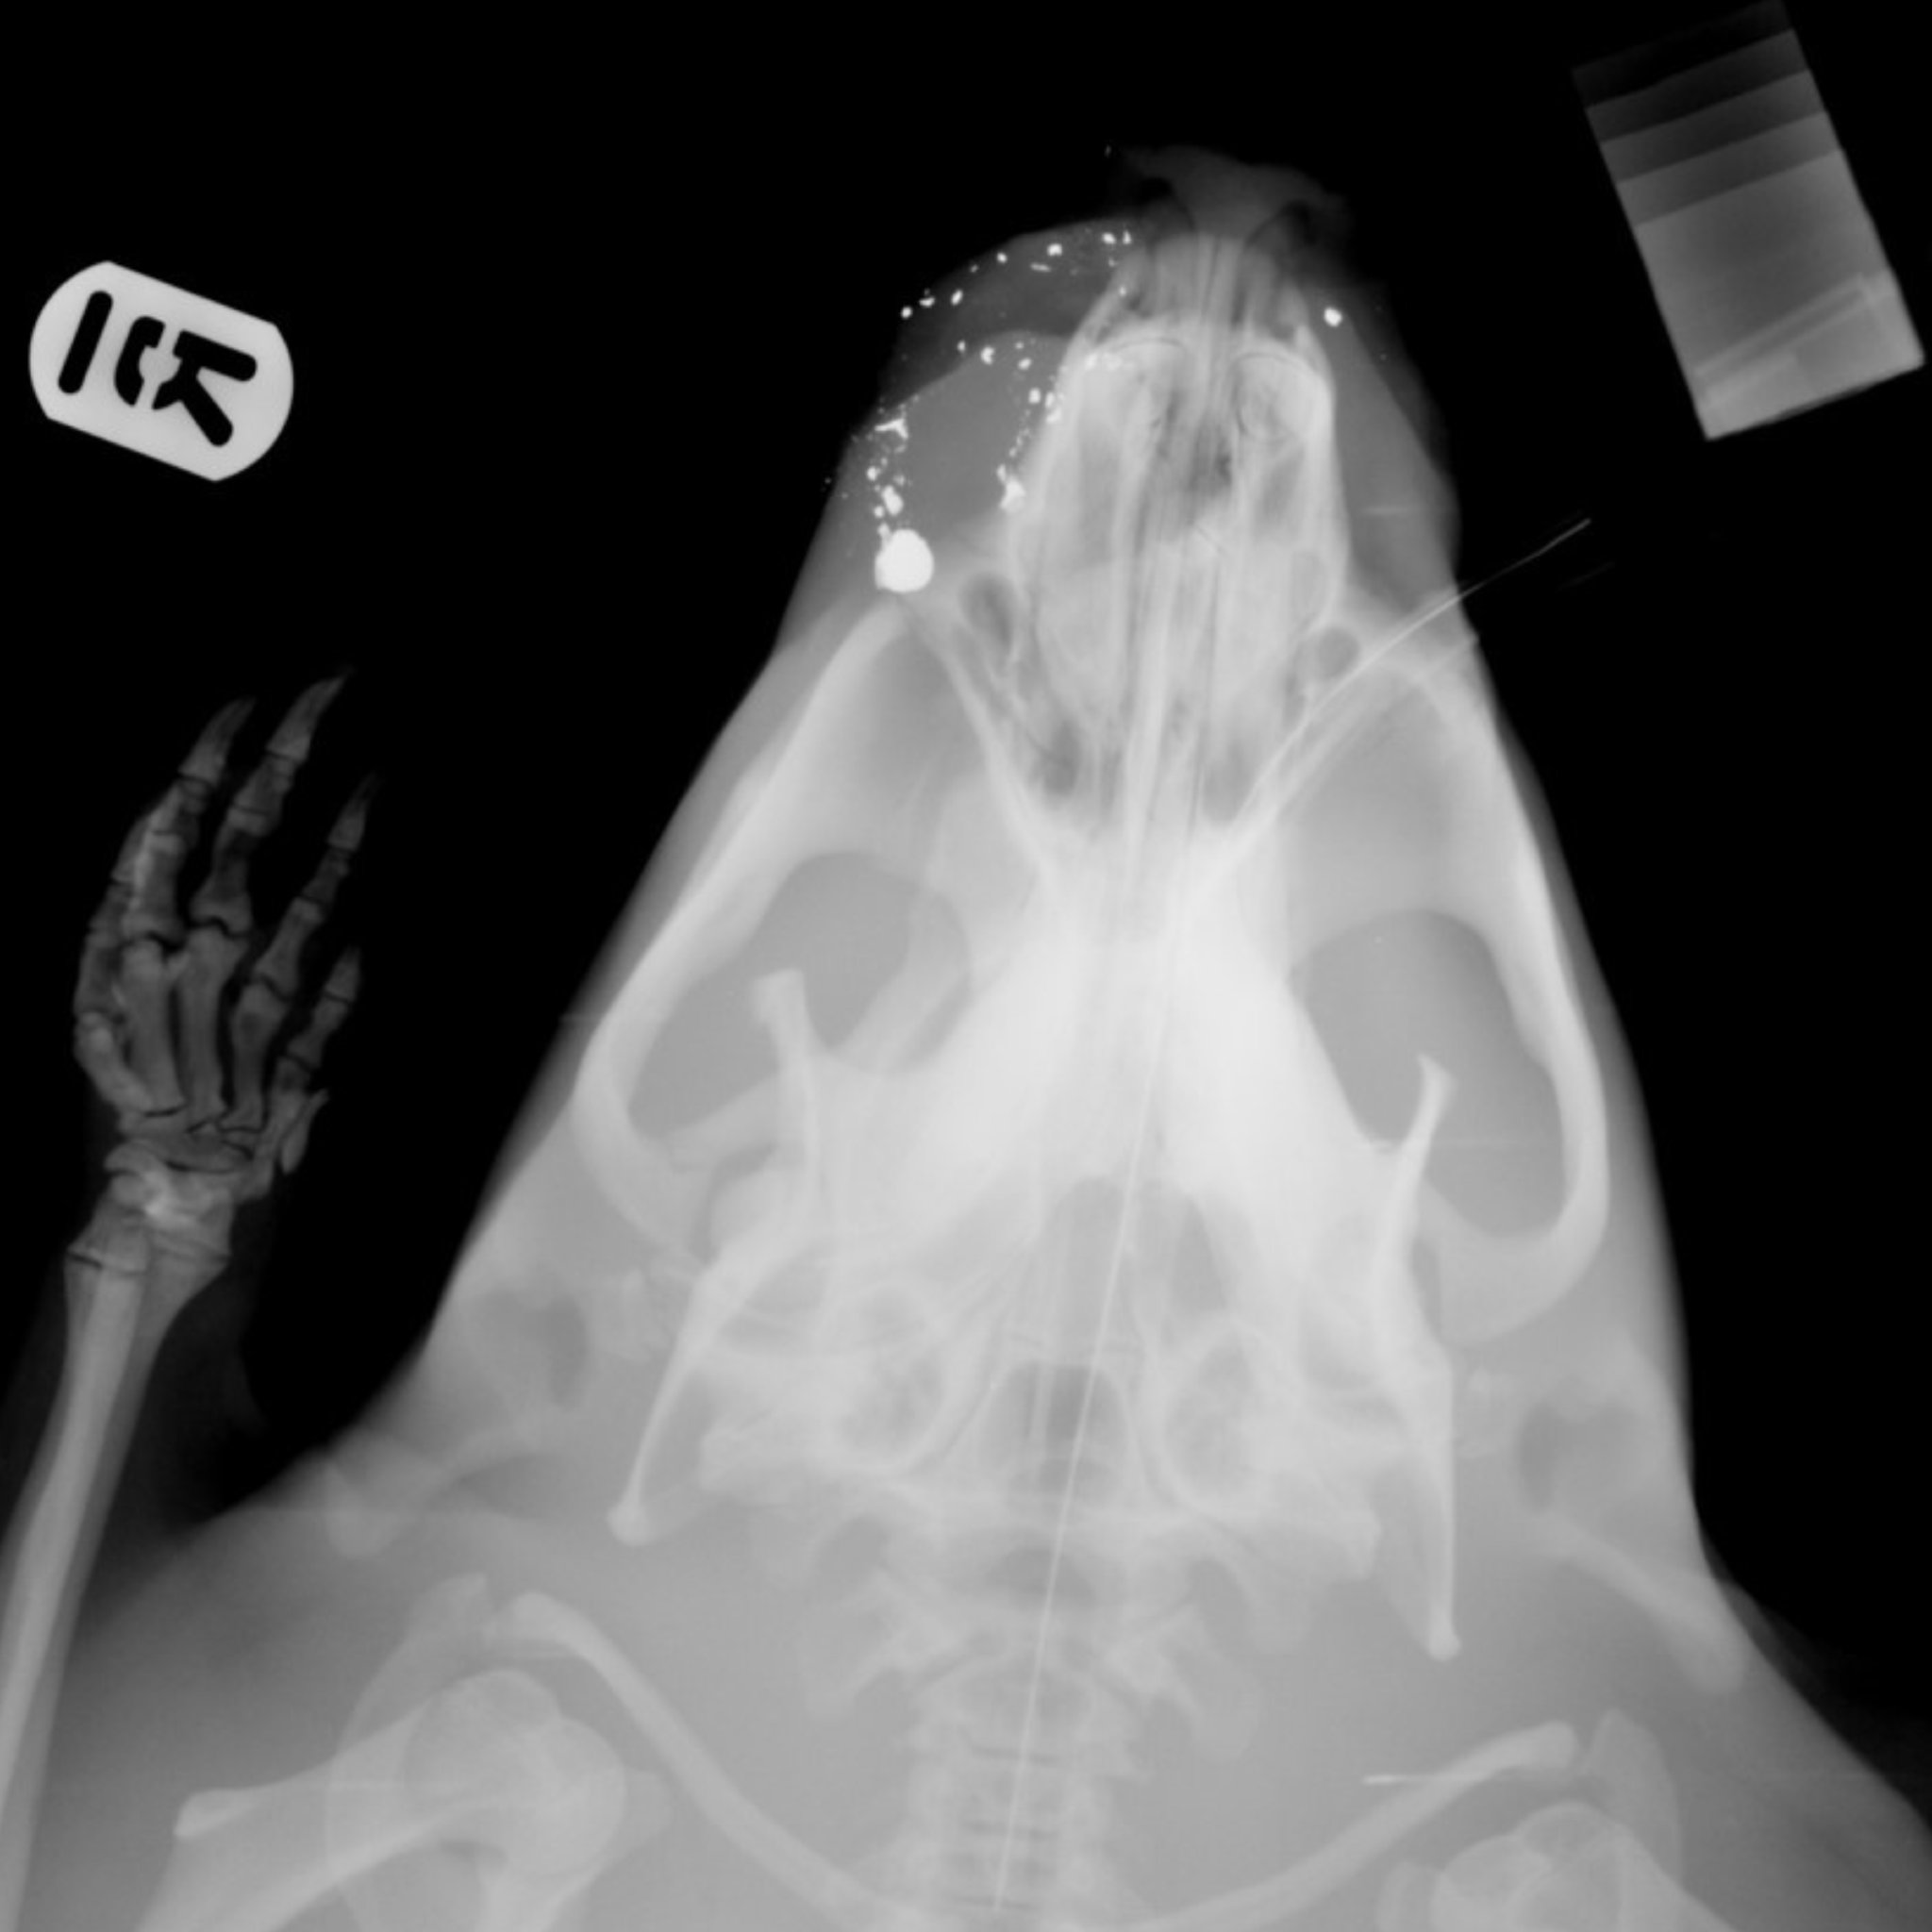

Fig was discovered by a member of the public with wounds to his face, two missing incisors and peppered with shrapnel.

He was taken to the SSPCA’s National Wildlife Rescue Centre, where he received extensive care and was able to grow his teeth back.